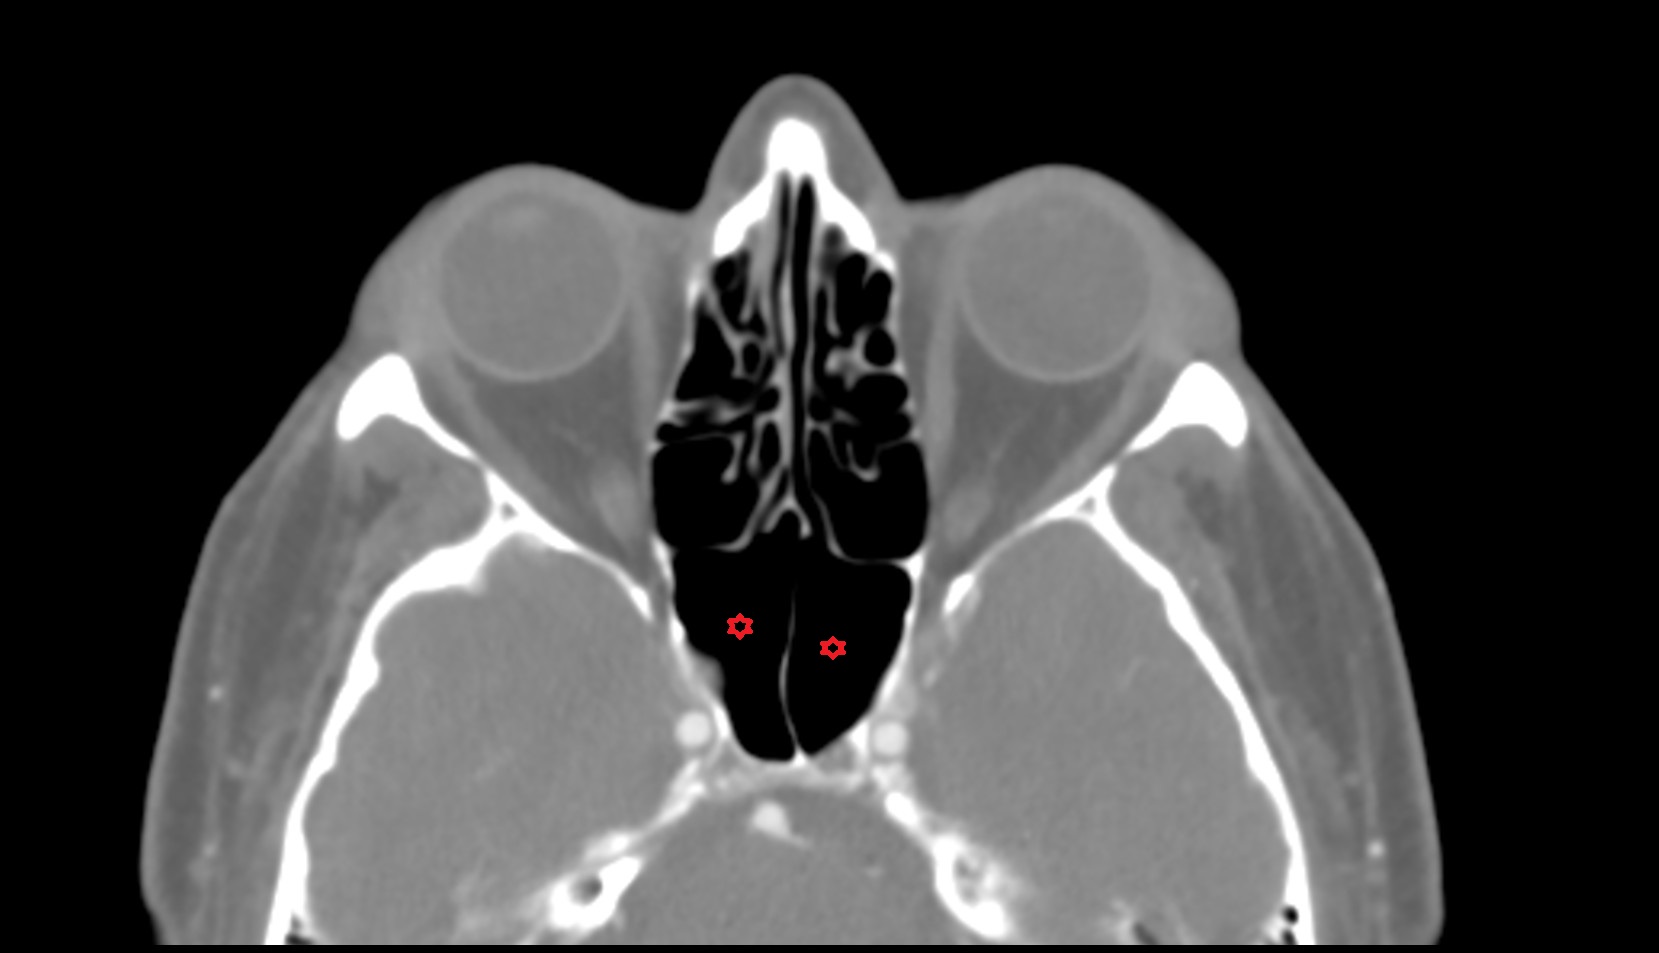

- Meckel’s cave (Trigeminal cave)